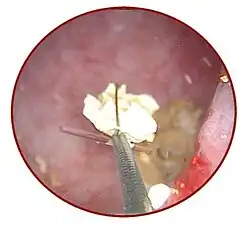

Mit einem Miktionszystourethrogramm kann ein krankhafter Rückfluss von Urin von der Blase in die Harnleiter und die Niere dargestellt werden. Die Ureteroskopie ist ein endoskopisches Verfahren zur direkten bildlichen Darstellung des Lumens und gegebenenfalls auch zur Behandlung (minimalinvasive Chirurgie) bestimmter Harnleitererkrankungen wie Steinen. Das Endoskop kann dabei entweder über die unteren Harnwege (retrograde Ureteroskopie) oder, wenn dies aufgrund von Verlegungen nicht möglich ist, durch die Bauchdecke und das Nierenbecken in den jeweiligen Harnleiter eingeführt werden (antegrade Ureteroskopie).[51] Die Ureteroskopie ist besonders bei Steinen[52] sowie bei Tumoren diagnostisches Mittel der Wahl, allerdings sind bei Tumoren zur Begutachtung der Umgebung (insbesondere der Lymphknoten in Hinblick auf Metastasen) zusätzlich CT- oder MRT-Untersuchungen notwendig.[53]

Die häufigste Ursache für Verlegungen des Harnleiters sind Harnleitersteine.[74] Da die Passage des Urins durch den Harnleiter relativ rasch verläuft, entstehen Harnleitersteine meist im Bereich der Niere als Nierenstein und verkeilen sich dann bei der Passage im Harnleiter. Harnleitersteine können nach Art ihrer Entstehung verschiedene chemische Zusammensetzungen haben.[75] In den Industrieländern beträgt die Inzidenz von Harnsteinen etwa 10 %, mit steigender Tendenz.[74] Auch bei Hunden und Katzen sind Harnsteine die häufigste Ursache für Harnleiterobstruktionen,[76] aber prinzipiell können alle Tierarten betroffen sein. Es gibt Fallberichte zu Pferden,[77] Kaninchen,[78] Meerschweinchen,[79] Zwergottern,[80] Delfinen[81] und Vögeln[82]. Durch krampfartige Muskelaktionen versucht der Harnleiter, die Steine weiter zu transportieren, was als schmerzhafte Harnleiter-Kolik wahrgenommen wird. Die wehenartigen heftigen Schmerzen strahlen je nach Lokalisation des Steins in den Rücken, den Bauch, die Leiste oder die Genitalien aus. Häufig kommt es auch zu Blutbeimengungen im Urin (Mikrohämaturie oder Makrohämaturie).[74] Bei erschwertem Abfluss hypertrophiert die Uretermuskulatur oberhalb des Hindernisses rasch. Die Steine werden heute vor allem ureteroskopisch bzw. antegrad ureteroskopisch mittels Laser-Lithotripsie oder von außen mittels extrakorporaler Stoßwellenlithotripsie zertrümmert.[83] Führt dies nicht zum Erfolg, muss der Stein durch Eröffnung des Harnleiters (Ureterolithotomie) entfernt werden, die heute vor allem laparoskopisch erfolgt.[84] Hier besteht anschließend immer die Gefahr der Entstehung von narbigen Einengungen (Strikturen), weshalb meist auch eine Harnleiterschienung durchgeführt wird.[85] Harnleiterschienen werden auch bei Harnleiterstrikturen anderer Ursache oder bei Nierensteinen eingesetzt.[86]

Obwohl Harnsteine schon in der Antike bekannt waren und ihre Entfernung aus der Blase beschrieben war – im Mittelalter gab es dafür den Beruf des „Steinschneiders“ (Lithotomus) – dauerte es bis in die 1980er Jahre, bis die technischen Möglichkeiten einer Uretersteinzertrümmerung im Körper ausgereift waren.[120] Die erste Harnleiterschienung führte Gustav Simon bereits im 19. Jahrhundert durch,[121] die heute noch eingesetzten Doppel-J-Schienen wurden erstmals 1967 von Paul D. Zimskind und Mitarbeitern beschrieben.[122] 1981 gelang die erste endoskopische Steinentfernung mit einem Greifkörbchen, bis dahin mussten Harnleitersteine mittels offener Ureterolithotomie chirurgisch behandelt werden. 1983 konnten Jeffry L. Huffman und Mitarbeiter an der California State University, Bakersfield erstmals einen Stein mit einem Ultraschall-Lithotripter zertrümmern, 1990 kam erstmals ein pneumatischer Lithotripter und 1995 erstmals ein Festkörperlaser auf der Basis von mit Holmium dotiertem Yttrium-Aluminium-Granat (Ho:YAG) zur Uretersteinzertrümmerung zum Einsatz.[123]